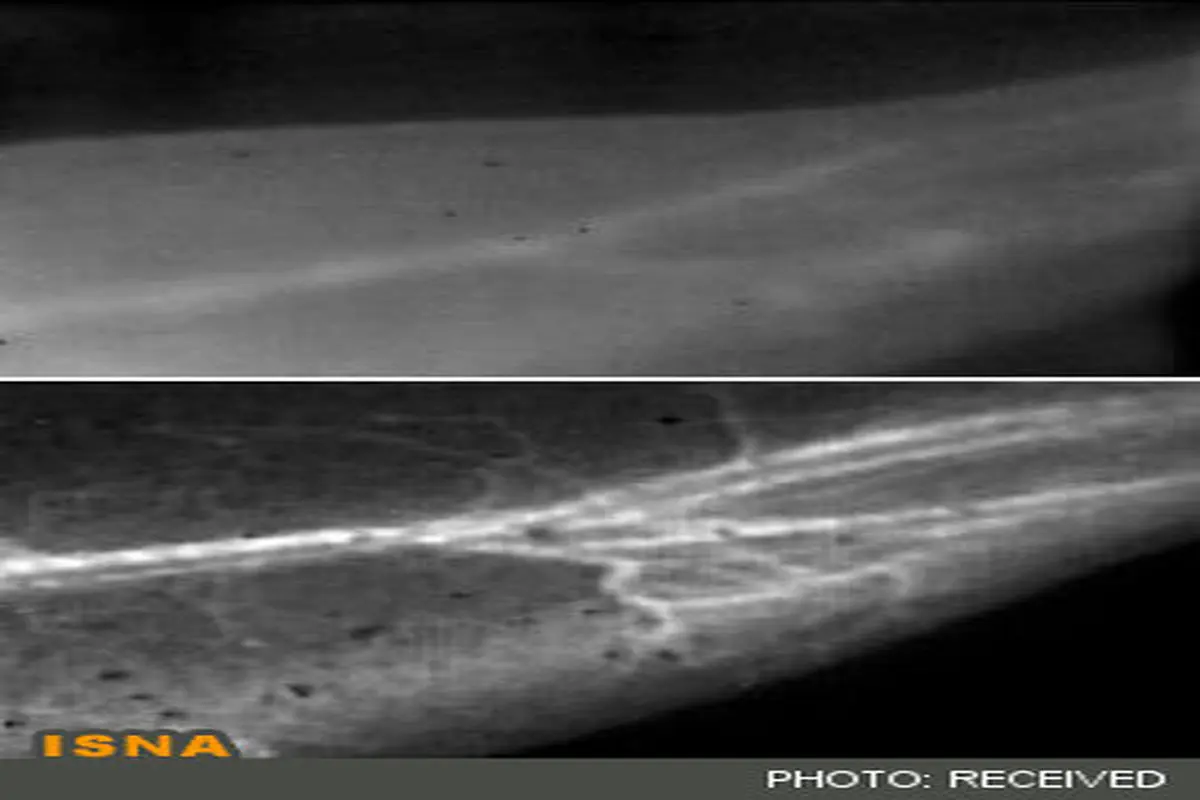

تصویربرداری بیسابقه از جریان خون

دانشمندان دانشگاه استفورد روشی در تصویربرداری فلورسانس ابداع کردهاند که دیدن رگهای خونی حیوانات را با وضوح بیسابقهای میسر میکند.

به گزارش سرویس فناوری ایسنا، وضوح تصاویر در این روش به حدی است که مقایسه آن با تصاویر گرفته شده با روشهای مرسوم به منزله پاک کردن بخار از روی شیشه عینک به نظر میرسد.

این روش که تصویربرداری نزدیک به مادون قرمز یا همان NIR-II نام گرفته است، در مرحله اول شامل تزریق نانولولههای کربنی محلول در آب در جریان خون موجود زنده است. این محققان سپس یک باریکه نور لیزر، نوری در محدوده نزدیک به مادون قرمز با طولموجی در حدود هشت دهم میکرون را به موجود زنده که در این مورد یک موش است، میتابانند.

اصل بازتابندگی ذاتی نانولولهها در طولموجهایی بلندتر از روشهای مرسوم تصویربرداری نکته اساسی در دستیابی به این تصاویری با وضوح فوقالعاده حتی در رگهای ریز خون است. نور با طولموج بلندتر کمتر پراش شده و بنابراین تصاویری واضحتر را از رگها ایجاد میکند.

از مزایای دیگر آشکارسازی نور با چنین طولموج بلندی این است که آشکارساز، مزاحمتهای پیشزمینه را کمتر ثبت میکند، زیرا که بدن در این طولموج از خود خاصیت خودبازتابی نشان نمیدهد. علاوه بر ایجاد کوچکترین جزئیات در تصویر، این روش سرعت تصویربرداری بالایی داشته و محققان را قادر میکند تا جریان خون را بطور آنی ثبت کنند.

قبل از این، دستیابی به اطلاعات جریان خون و تصویر واضح از رگ بطور همزمان میسر نبود. به همین دلیل این روش بویژه در مطالعه اختلالات شریانی نظیر اینکه چگونه انسداد و انقباض شریان که از عوامل سکته قلبی هستند، بر جریان خون موثرند، میتواند بکار گرفته شود.

این دانشمندان با مطالعه ساختار رگهای یک موش آزمایشگاهی مبتلا به بیماری شریانی با استفاده از روش تصویربرداری مذکور به این نتیجه رسیدهاند که این فناوری، ابزاری مفید برای مطالعه اندامهای حیوانات کوچک است و درک بهتری از برخی بیماریهای رگ و پاسخ آنها به روشهای درمان، بوده و در نهایت منجر به ابداع روشهای درمانی بهتر خواهد شد.

این روش بدلیل نفوذ چند سانتیمتری نور نزدیک به مادون قرمز در بدن قابل کاربرد برای انسان نیست، اما ابزاری قدرتمند برای مطالعه حیوانات آزمایشگاهی از طریق جایگزینی یا تکمیل روشهایی نظیر اشعه ایکس، CT، MRI و Laser Doppler خواهد بود.

این دانشمندان، جزئیات نتایج کار تحقیقاتی خود را در مجله «Nature Medicine» منتشر کردهاند.